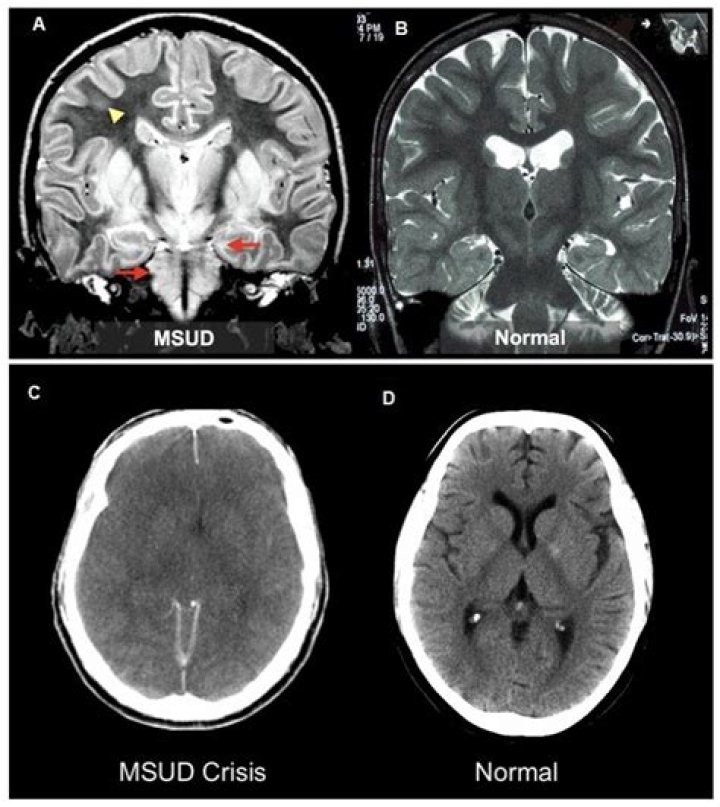

If untreated, life-threatening coma or respiratory failure could occur within 7 to 10 days and most will die within several months. Upon any lapse of treatment, classic MSUD can cause brain damage.